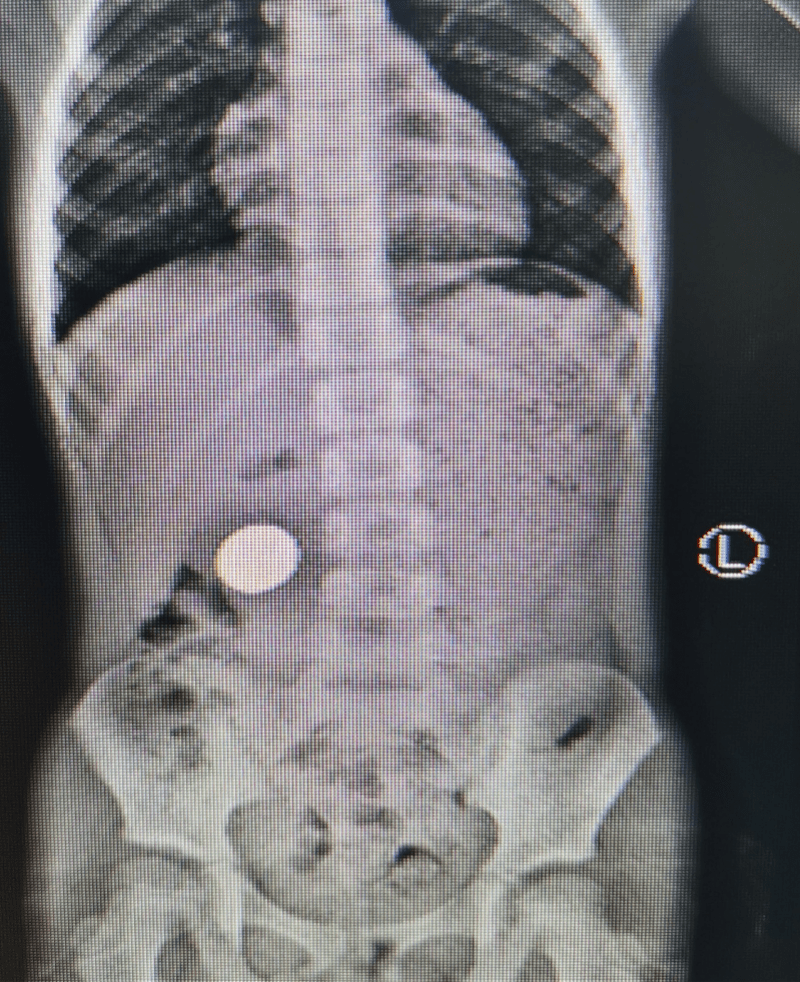

5岁的小余(化名)持续性上腹痛伴恶心、呕吐1年多 , 近2天加重后来深圳市中西医结合医院就诊 , 经X线检查发现 , 小余右侧中腹部见“硬币”样消化道致密影长约30mm , 考虑消化道异物 。

文章图片

患者腹平片